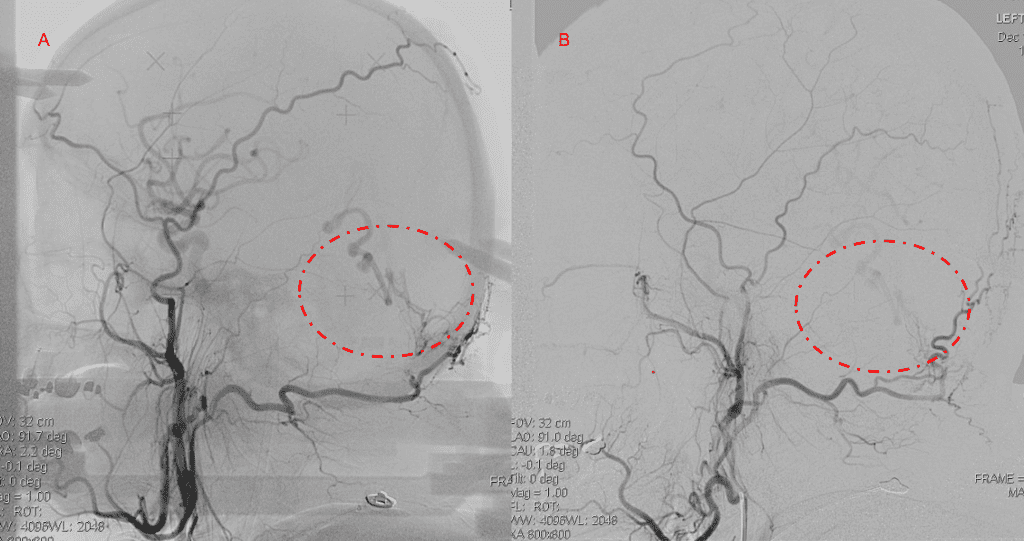

Embolization was successful at immediately reducing the pressure into the Aneurysmal Varix with greater than 90% reduction in A-V shunts. After an intensive period of critical care monitoring and care for her initial brain hemorrhage, she made a near complete recovery with mild intermittent left sided paresthesias and generalized deconditioning. After receiving inpatient and outpatient Acute Rehabilitation, Physical, and Occupational therapy, she completely recovered all of her Activities of Daily Living (ADLs) at 3 months and achieved an modified Rankin Scale (mRS) of 0. On follow-up angiography, small residual low flow A-V shunts were identified and targeted for Gamma Knife Radiosurgery (Figure 5 and 6).

Figure 5. Bilateral ECA Lateral angiograms (A and B) demonstrates small residual indirect supply To the AVM from the bilateral Occipital arteries.